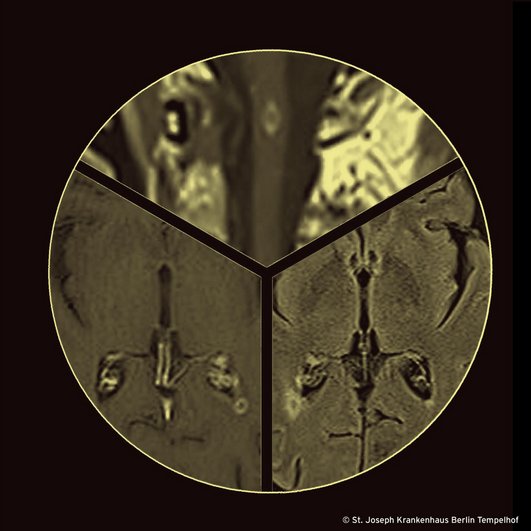

Bildgebung Neuroachse: Die MRT des Gehirns zeigt jetzt eine lineare subependymale Kontrastmittelanreicherung des dorsalen Anteils des Pars centralis sowie des Trigonums des linken Seitenventrikels. Hinzu kommen insgesamt sieben, maximal 7mm durchmessende, ringförmig kontrastmittelanreichernde Herde ohne relevantes Umgebungsödem. Sie sind in den nativen T1w-Aufnahmen nicht abgrenzbar. Fünf der Läsionen befinden sich supratentoriell im subkortikalen und periventrikulären Marklager sowie im Corpus und Splenium des Balkens. Zwei davon liegen infratentoriell im Hirnstamm. Die Herde sind nicht diffusionsgestört. Es findet sich kein meningeales Enhancement und es gibt keine Zeichen einer Liquorzirkulationsstörung oder einer Ischämie. Hinzu kommen mehrere ringförmig kontrastmittelanreichernde Herde im cervikalen und thorakalen Myelon, die im Oktober definitiv noch nicht vorhanden waren.

Zusammengefasst ist die Anzahl der Herde, sowie deren Durchmesser leicht progredient und es gibt neue Herde im Myelon. Keiner der Herde ist einer unkritischen Biopsie zugänglich. Extraneurale Bildgebung: Die Computertomogramme von Thorax und Abdomen sind unauffällig, lediglich im linken Hilus findet sich ein kleiner Lymphknoten.